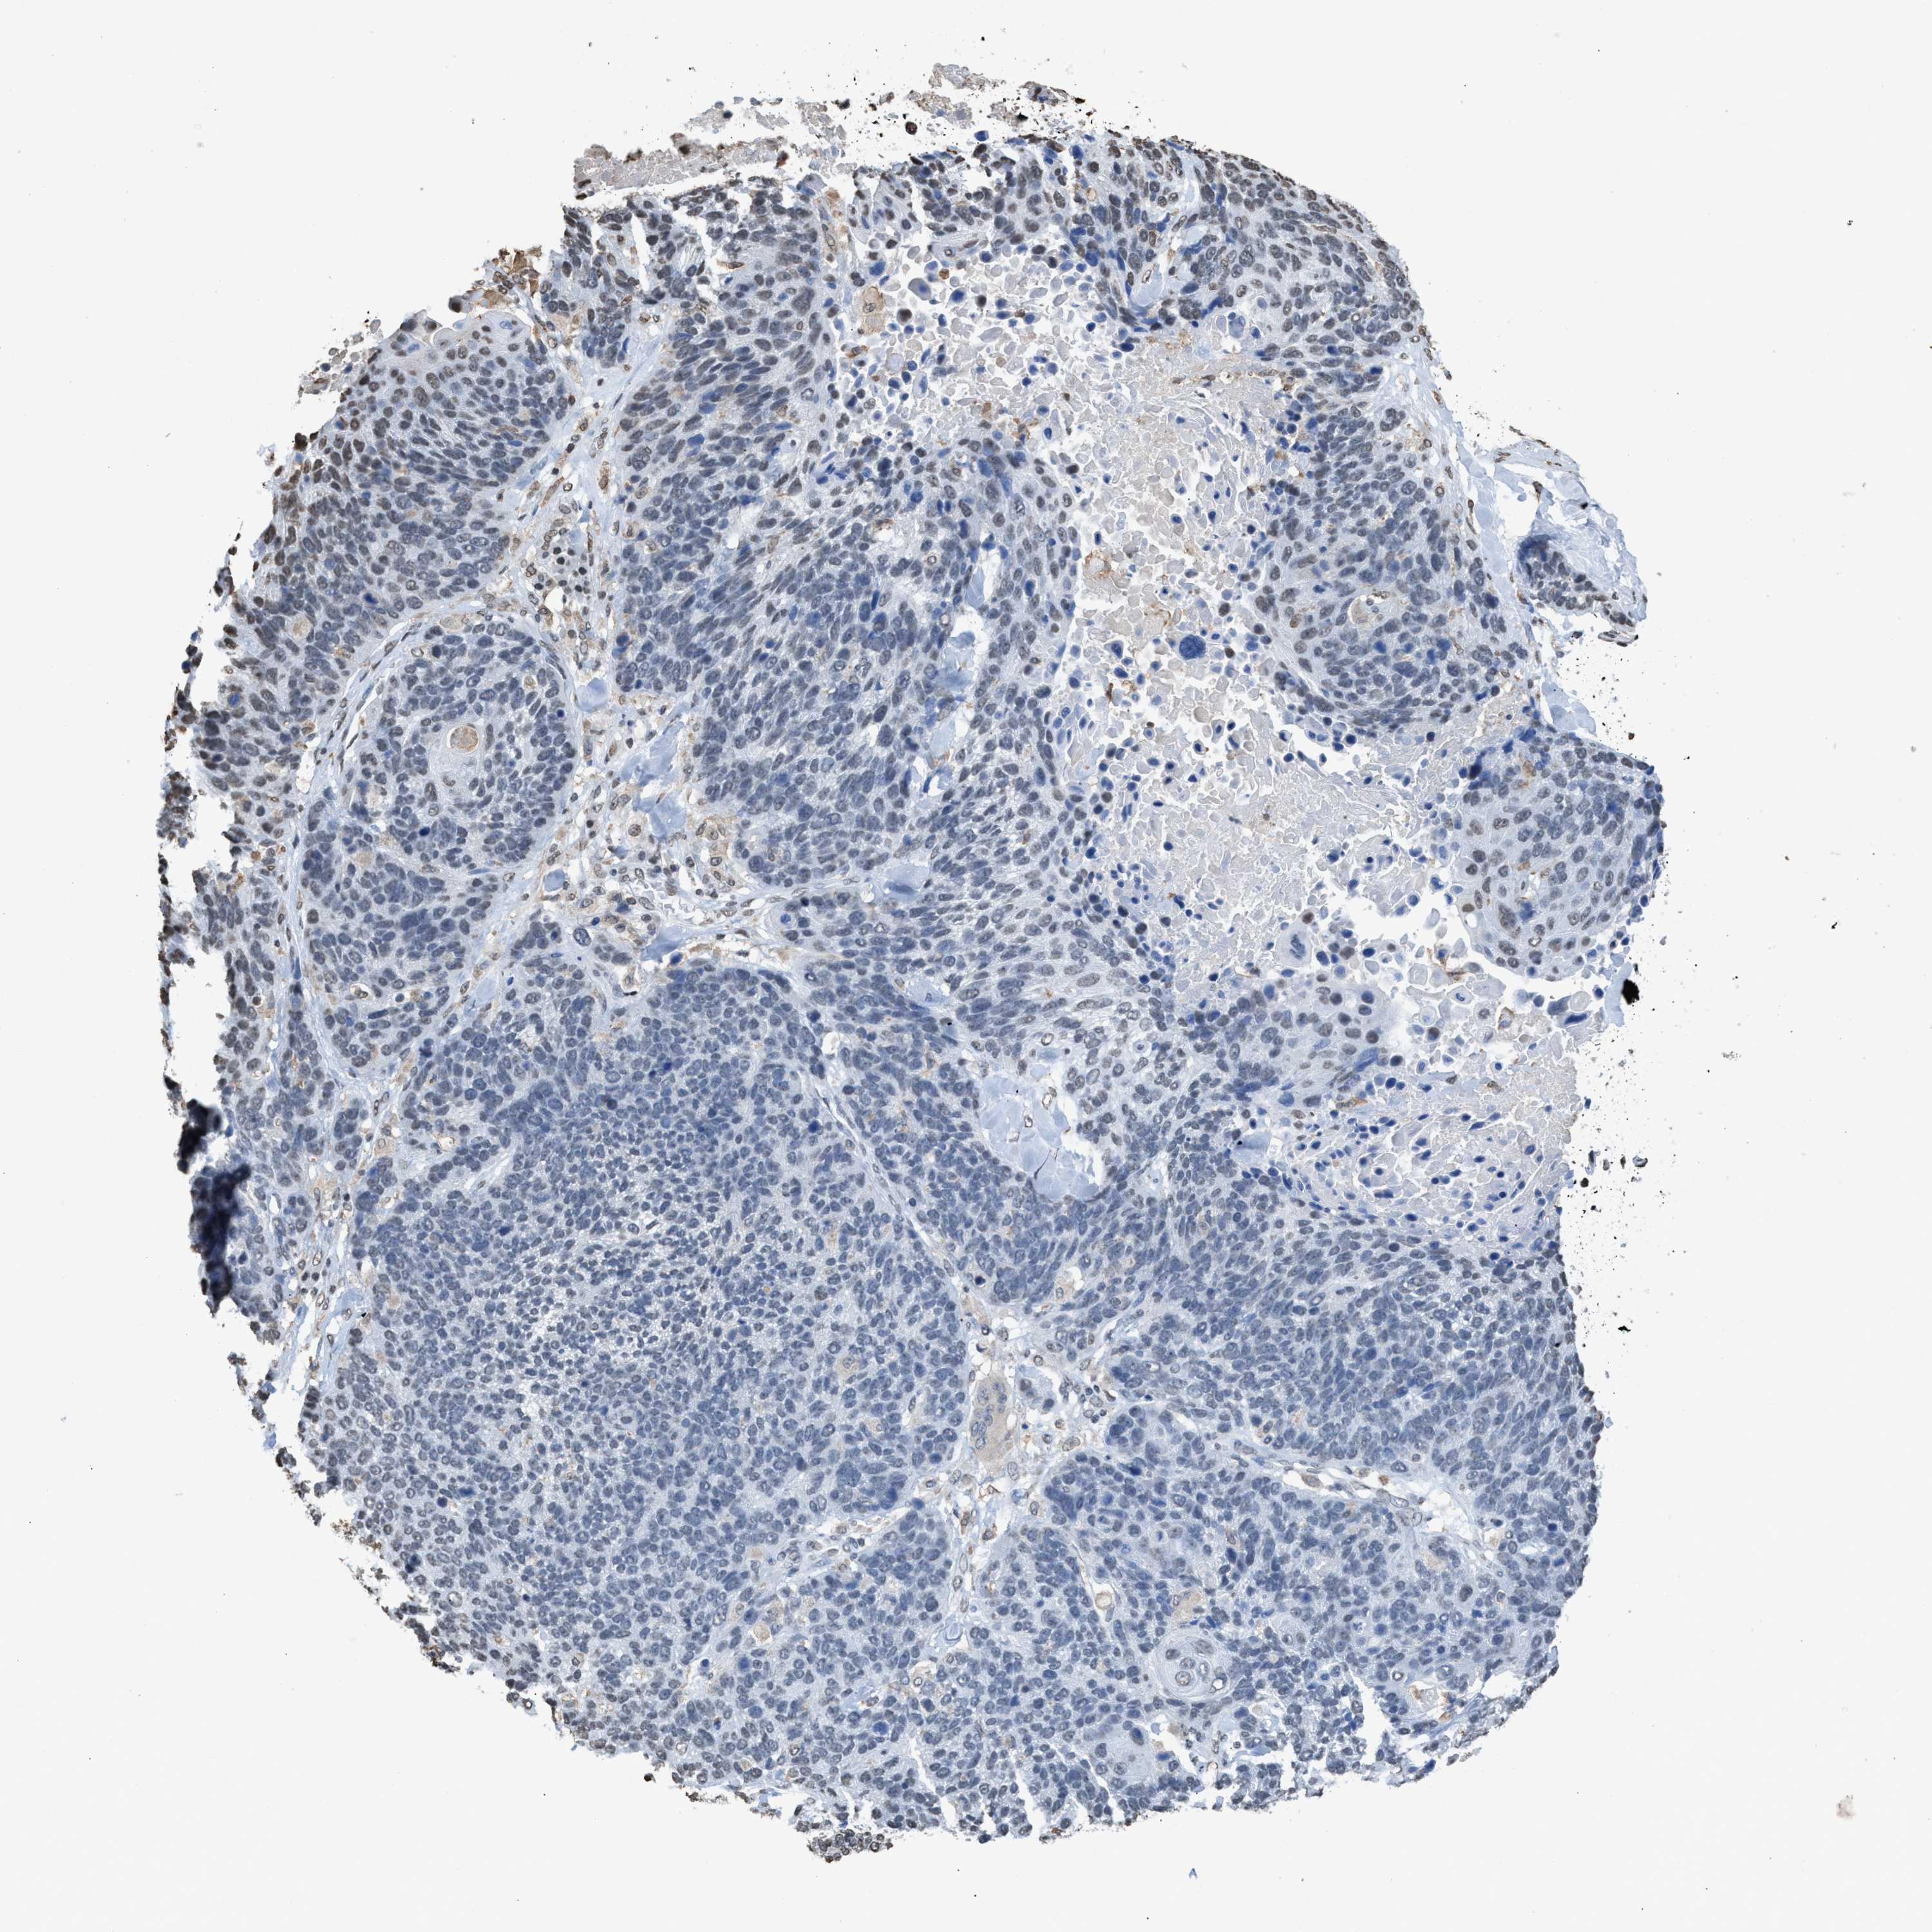

CANCER LUNG CANCER Show tissue menu

LUAD TCGA LUAD VALIDATION LUSC TCGA LUSC VALIDATION PROTEIN LUAD CPTAC PROTEIN LUSC CPTAC PROTEIN EXPRESSION